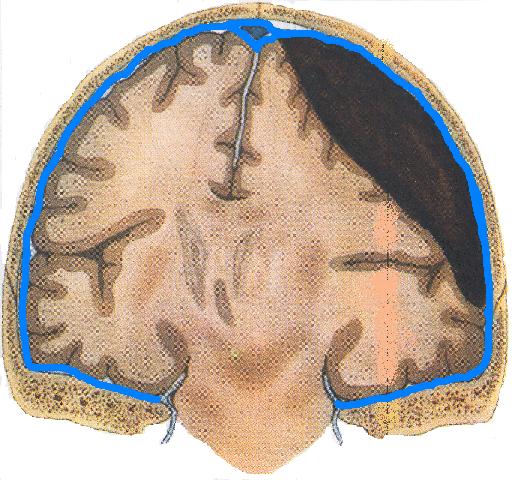

Внутричерепные кровоизлияния у новорожденных презентация - 92 фото